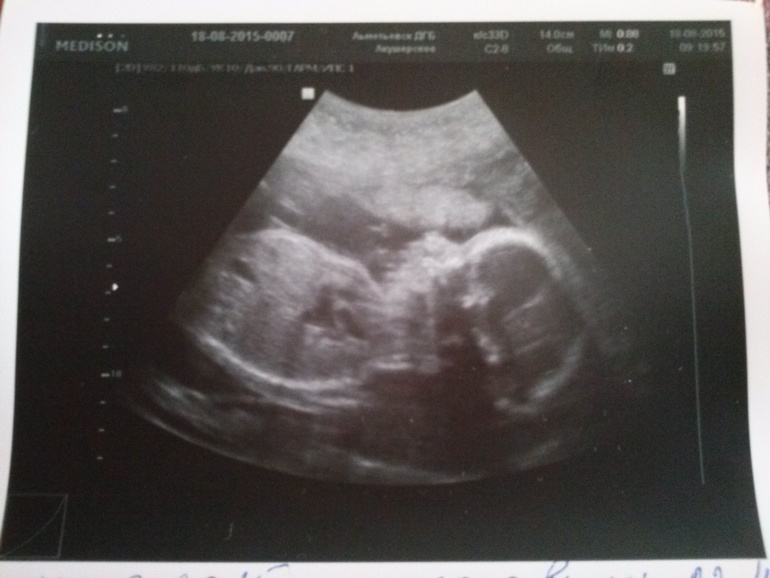

Наше 2е узи))))

Самое главное, что соответствуем сроку 22,4. Это на 3 дня меньше, чем в 1й скрининг, и на 6 дней больше чем по месячным.вес 495гр )))) ПДР поставили на 18.12.15. И еще... ничего не отвалилось))) у нас по прежнему мальчик)))) ну и фоточку сделала